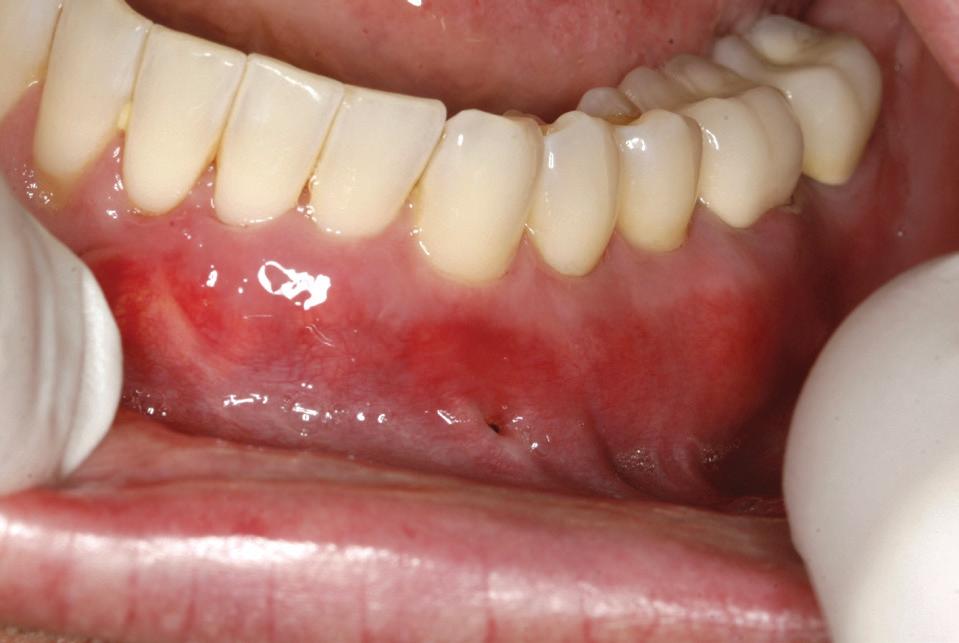

Un pacient caucazian în vârstă de 77 ani s-a prezentat la clinica autorului după cinci ani în care nu a fost la niciun control stomatologic. Examinarea clinică a arătat o pierdere semnificativă de os, parodontită cronică și multiple edentații care au destabilizat ocluzia. Pacientul a raportat sensibilitate la rece la nivelul primului molar drept inferior nr. 46, în special la ingerarea de lichide reci. Radiografia periapicală a confirmat constatările examenului clinic; în

plus, s-a detectat și prezența unei carii radiculare la nivelul rădăcinii distale a aceluiași molar, cu răspuns pozitiv la testul de sensibilitate (fig. 1-2).

1. Situația clinică inițială.